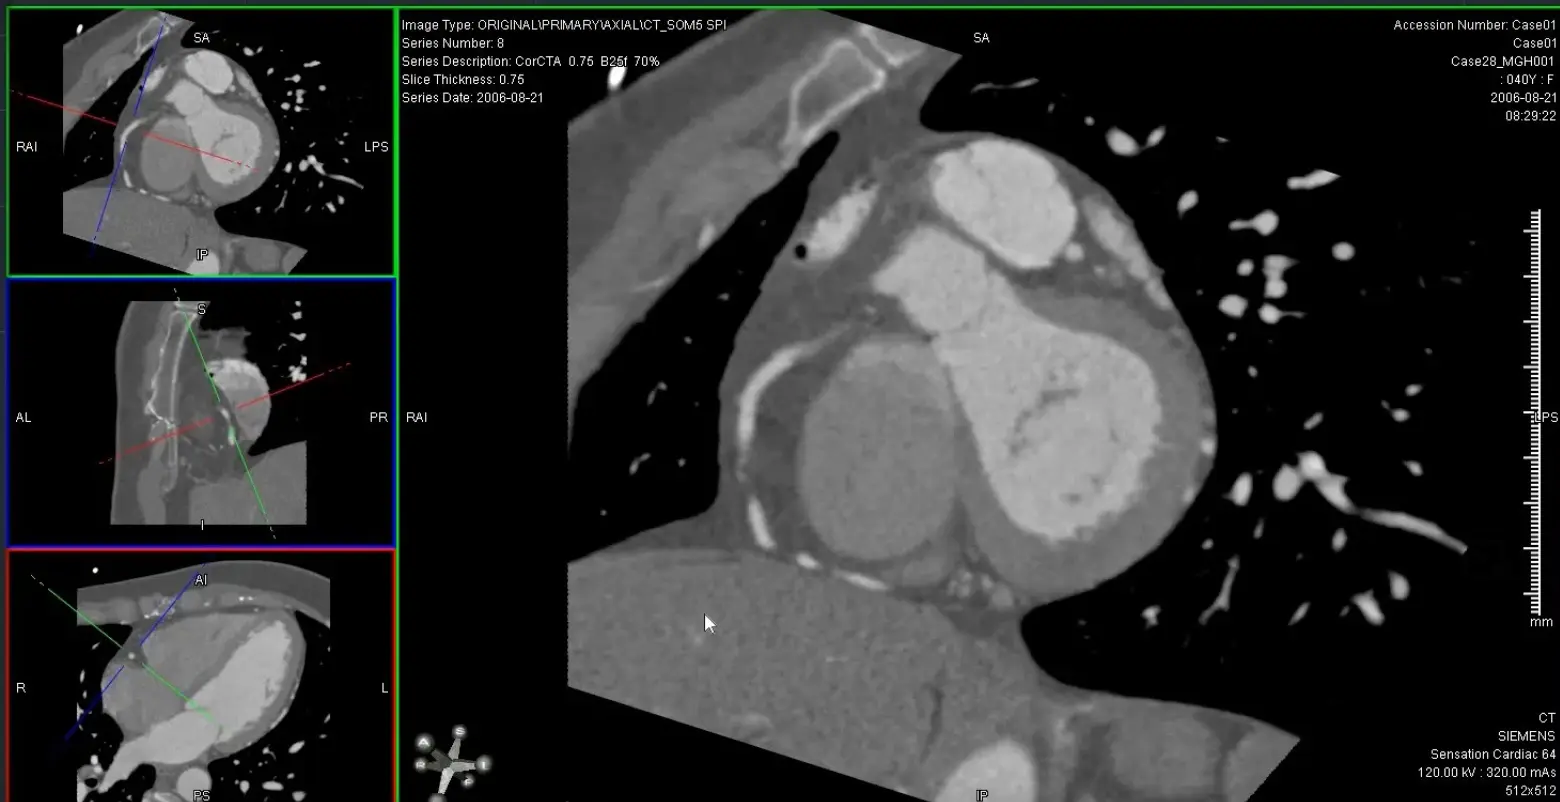

- Generate orthogonal views of coronary arteries using MPR (e.g. 0.5 mm thickness) to be able to evaluate luminal narrowing

- → Align 2 view through the long axis

- → Then double click on the remaining plane to see the SAX and evaluate for luminal stenosis

- Use the SAX images to measure 📐 luminal stenosis

MPR of ‘C’ view of RCA

Above, but changed to MIP